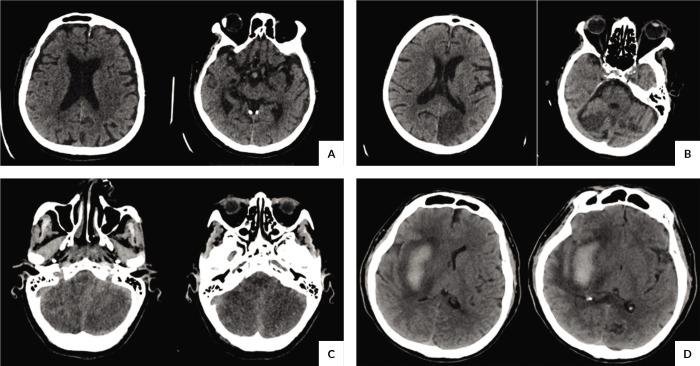

We conducted a cross-sectional study analyzing CT images of COVID-19 patients with neurological symptoms. Among 51 included patients, plain CT scans were predominantly used, revealing no acute infarcts or hemorrhages in the majority, while frontal lobe involvement was notable in cases with pathology. Chronic infarcts or ischemic changes were observed in over half of the cases, primarily affecting the anterior circulation. Only one case of meningitis was documented.

In the final analysis, 51 patients met the inclusion criteria out of the initial 64 enrolled. The study population, predominantly male with a mean age of 58.02 ± 20.87 years, mainly comprised patients solely diagnosed with COVID-19. Plain CT scans were favored over contrast-enhanced scans (76.50%, n = 39). While most patients had no acute infarcts or hemorrhages, the frontal lobe was commonly affected among stroke patients (9.8%, n = 5). Additionally, a significant portion of patients without acute stroke findings exhibited chronic infarcts or ischemic changes (57.69%, n = 15).

This study sheds light on the radiological patterns of CNS involvement in COVID-19 patients, highlighting frequent frontal lobe involvement possibly attributed to hypercoagulability and endotheliitis. Further research with larger sample sizes and MRI utilization is recommended to enhance our understanding of CNS manifestations in COVID-19. This study contributes to understanding COVID-19 neurological sequelae, particularly in terms of radiological patterns, among patients presenting with neurological symptoms. The findings highlight the need for comprehensive evaluation and management of neurological complications in COVID-19 patients.